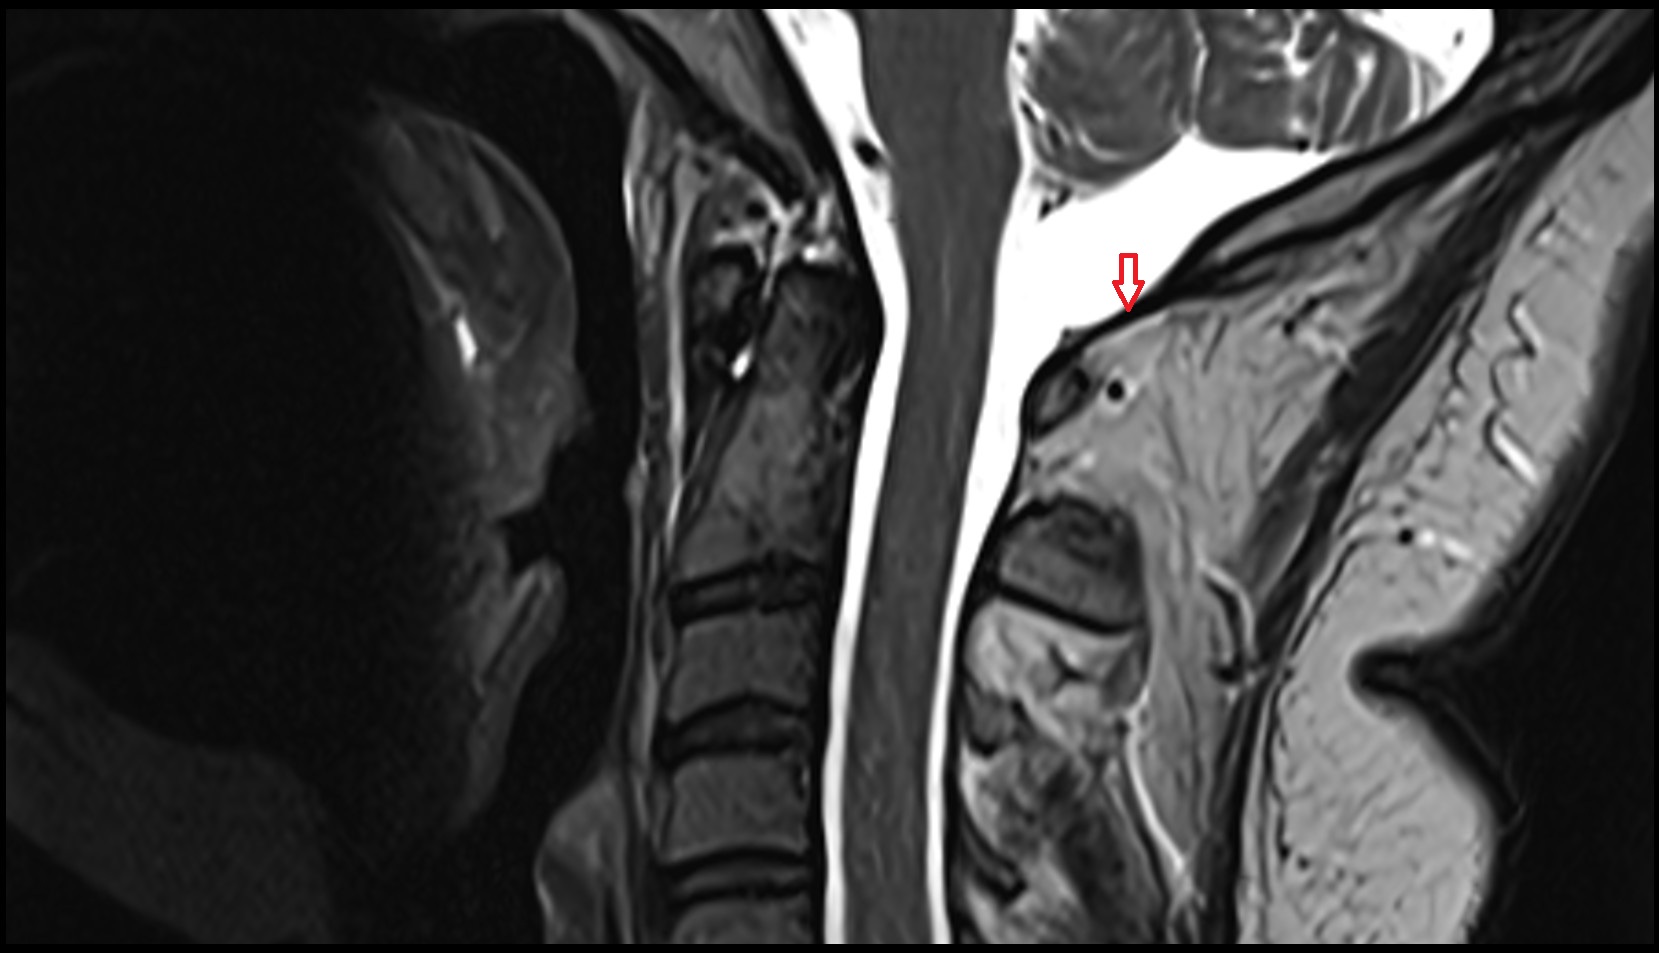

- Spinal cord

- Upper cervical spinal cord

- Body of vertebra

- Intervertebral Disc